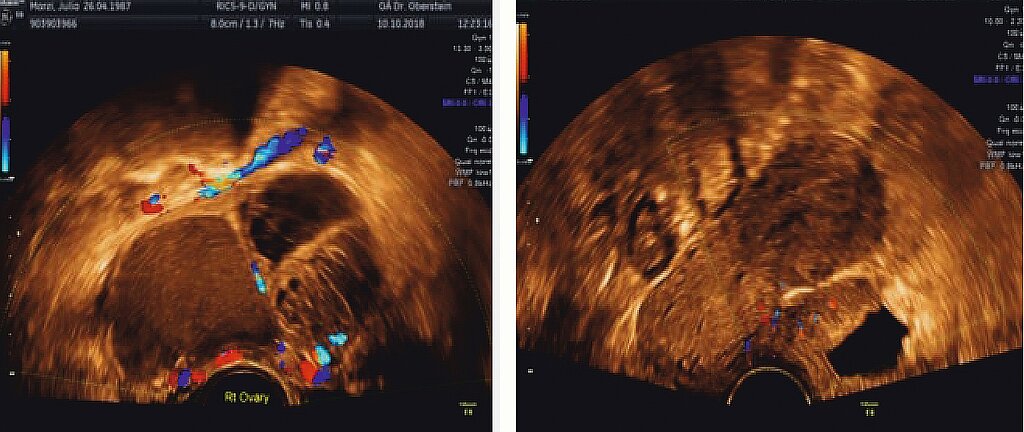

Die heute wohl wichtigste diagnostische Methode neben der akribischen Anamneseerhebung und der sachgerechten gynäkologischen Untersuchung ist die Transvaginalsonographie (TVS). Durch die systematische Befunddarstellung, wie in den IDEA- und MUSA-Konsensuspapieren [31, 32] aufgeführt, sollte es bei etwas Training in Klinik und Praxis möglich sein, insbesondere bei tief-infiltrierender Endometriose, eine zutreffende Diagnose zu stellen. Hierzu kann man heute sogar die Darstellung der sacralen Nervenwurzeln zählen. Beispiele für das ovarielle Endometriom sowie die Blasenendometriose sind in (Abb. 4) gegeben.

Bei Verdacht auf eine pelvine Endometriose sollte auch eine beidseitige Nierensonographie vorgenommen werden, da durch eine extrinsische oder intrinsische Ureterendometriose relativ häufig eine meist symptomarme Hydronephrose entstehen kann, die im schlimmsten Fall zu einer stummen Niere führt. Dieses Vorgehen ermöglicht bereits präoperativ eine Klassifizierung der Endometriose nach dem #Enzian-Schema (Abb. 5) [33], welches ein gutes Instrument für die einheitliche Beschreibung der Endometriose darstellt und außerdem abschätzen hilft, wie ausgedehnt eine operative Therapie sein könnte und mit welchen Komplikationen gerechnet werden sollte.

Bei der TVS kann durch das Einführen des Schallkopfes wiederum ein „pain mapping“ sowie bei gleichzeitiger abdominaler Palpation das Ausmaß von Verwachsungen und das damit oft verbundene Vorliegen eines „frozen pelvis“ ermittelt werden.